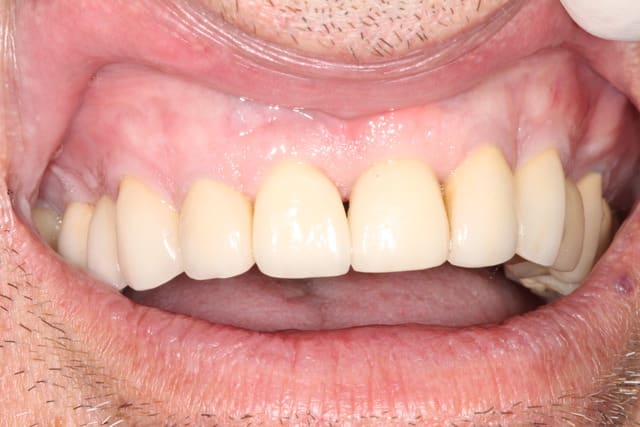

(petite précision c'est une photo à + de 2 ans post prothèse)

la réponse

c'est 11 en EII avec Mise en fonction immédiate mais... il y a 5-6 ans et comme beaucoup d'entre vous je me suis rendu compte que EII + MFI n'était pas une garantie pour éviter la fonte osseuse.

Pour prévenir la fonte osseuse, on m'a suggéré une technique, et c'est avec cette technique qu'il y a maintenant plus de 2 ans j'ai traité la 21

photo de controle vue vestibulaire et occlusale 8 mois post chir

puis à 2 ans post op

on constate que contrairement à la 11 surlaquelle il y a un affaissement de l'os vestibulaire

sur la 21 le volume est préservé

PS toutes les dents ont été couronné en unitaire il y a une dizaine d'années, mais patient qui bruxe beaucoup et qui a fracturé la 11 puis la 21

Si je peux me permettre, la 11 semble plus naturelle, car le zénith gingival est plus ovoide. La 21 possède certe plus de volume de tissu en vestibulaire, mais le collet gingivale est trop coronaire, effet de dent trapue.

L'ensemble est par contre sympa.